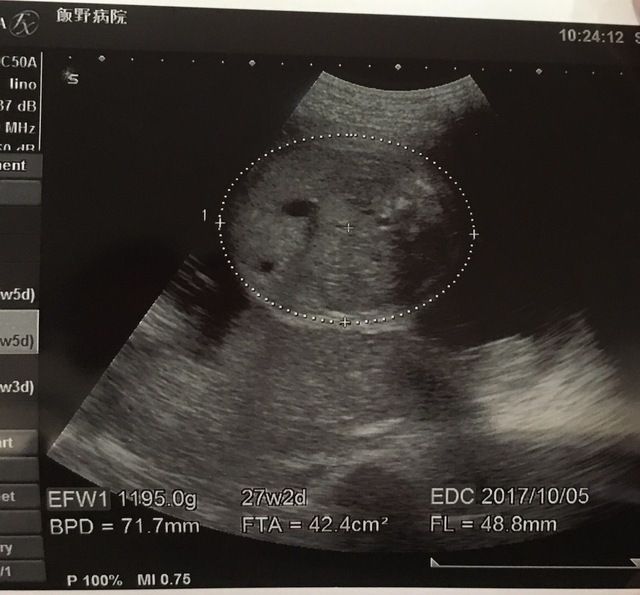

27週2日(27w2d・男の子)|かみきょ さん(31歳)

エコー写真撮影時のエピソード:

だんだんと背骨とか臓器が出来上がっていく過程が見えてうれしかったです。先生は一生懸命説明してくれるけど、いまいちよくわからない場合もあり…。

遠方に住む親にエコー写真を送ると成長がうれしいようでとても喜んでくれました。しばらく送らないと催促の連絡がくるぐらいでした。